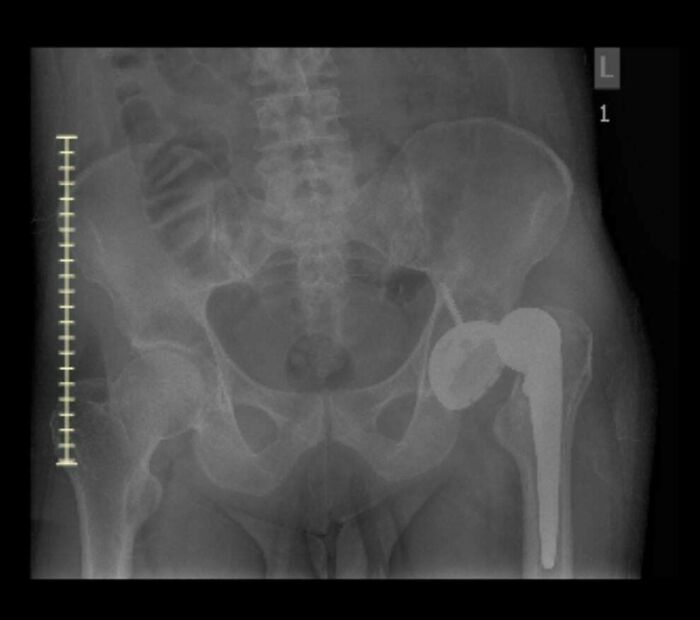

My Hip Died From Avn, Then I Woke Up In The Hospital Recovery Room Not Knowing The Replacement Was Dislocated

Some general info on my situation. Had developed on and off pain in my left leg/hip for years till it got so bad I couldn't put my full weight on it, which is when I got in for the first image showing an MRI slice of the dead hip. Eventually I was able to get the hip arthroplasty done. I awoke in recovery with my leg flat on the bed. I complained to the initial Nurse's & PT people that it felt weird & shorter than it should be. The Drs and surgeon said normally patients felt it was longer, but it felt shorter to me and those initial people after the surgery told me that what I felt was "normal"... I figured I just had a hip replacement & it'd be painful... ~1.5 months later they did a Xray & well, that's why I couldn't walk like I'd read I should have been able too. Anteriorly dislocated the whole time. I kept bringing it up about it feeling weird with the med related people I was seeing... I suppose I was a bit stoic & didn't give the right number of the pain that I felt. Just thought they knew better than me. I feel like I have a permanent muscle knot at this point.

All it took was an Xray to find the problem but they couldn't be bothered for 1.5 months?? (the doctors not the patient)